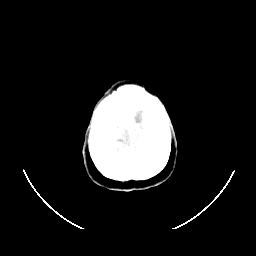

CT Study #1 -- Slice #28

[Home][Help][Clinical][Tour 1] Slice 28